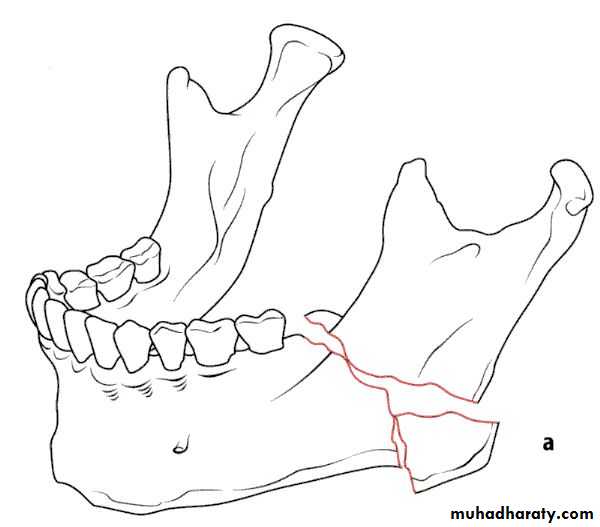

Class 34-classification according to the Direction of the fracture and favourability for the treatment

1- Horizontally favorable fracture.

2- Horizontally unfavorable fracture.

3- Vertically favorable fracture.

4- Vertically unfavorable fracture . This classification is aimed toward the angle and body fractures.

When the muscle pull resist fracture displacement , it is favorable(undisplaced), but, when the muscle pull distract the fragments away from each other resulting in displacement , it is unfavorable.

• Horizontally unfavorable fracture extends from the upper border downwards and backwards.

• Horizontally favorable fracture extend from upper border downwards and forwards.

• A vertically favorable fracture runs from the buccal plate anteriorly and backward through the lingual plate posteriorly.

• Vertically unfavourable fracture runs from the lingual plate anteriorly backward through the buccal plate posteriorly.